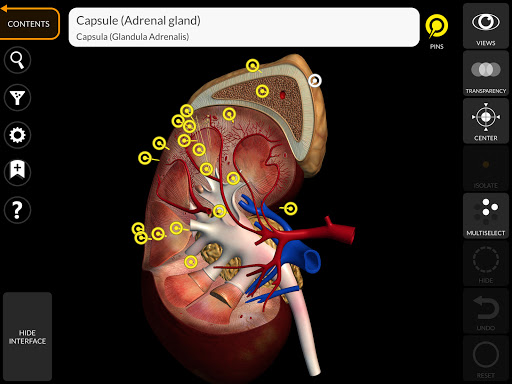

"Anatomy 3D Atlas" memungkinkan Anda mempelajari anatomi manusia dengan cara yang mudah dan interaktif.

Melalui antarmuka yang sederhana dan intuitif, Anda dapat mengamati setiap struktur anatomi dari sudut mana pun.

Model 3D anatomi sangat terperinci dan memiliki tekstur hingga resolusi 4k.

Pembagian berdasarkan wilayah dan tampilan yang telah ditetapkan sebelumnya memudahkan pengamatan dan studi bagian tunggal atau kelompok sistem dan hubungan antara organ yang berbeda.

saraf • Sistem pernapasan • Sistem pencernaan • Sistem urogenital (pria dan wanita) • Sistem endokrin • Sistem limfatik • Sistem mata dan telinga FITUR • Antarmuka yang sederhana dan intuitif • Putar dan perbesar setiap model dalam ruang 3D • Opsi untuk menyembunyikan atau mengisolasi satu atau beberapa model yang dipilih • Filter untuk menyembunyikan atau menampilkan setiap sistem • Fungsi pencarian untuk menemukan setiap bagian anatomi dengan mudah • Fungsi penanda untuk menyimpan tampilan khusus • Rotasi cerdas yang menggerakkan pusat rotasi secara otomatis • Fungsi transparansi • Visualisasi otot melalui tingkat lapisan dari yang superfisial hingga yang terdalam • Dengan memilih model atau pin, istilah anatomi terkait akan muncul • Deskripsi otot: asal, • Tampilkan/ Sembunyikan antarmuka UI (sangat berguna dengan layar kecil) MULTIBAHASA • Istilah anatomi dan antarmuka pengguna tersedia dalam 11 bahasa: Latin, Inggris, Prancis, Jerman, Italia, Portugis, Turki, Rusia, Spanyol, Mandarin, Jepang, dan Korea • Istilah anatomi dapat ditampilkan dalam dua bahasa secara bersamaan PERSYARATAN SISTEM • Android 8.0 atau yang lebih baru, perangkat dengan RAM minimal 3GB Reversi

• Sistem endokrin